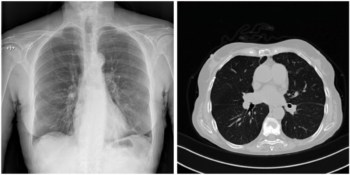

Angled light beams allow OCT to image deeper into skin

A new dual-axis optical coherence tomography system allows researchers to look deeper into biological tissue